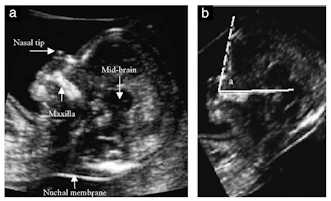

FMF , Yüz Açısı Değerlendirilmesi

Trizomili fetuslarda görülen burun kökündeki basıklığın ultrasonla fetal peryotta değerlendirilmesidir

Burun Kemiği Değerlendirilmesi Burun Kökü Değerlendirilmesi

Fetal Yüz Profil Değerlendirilmesi